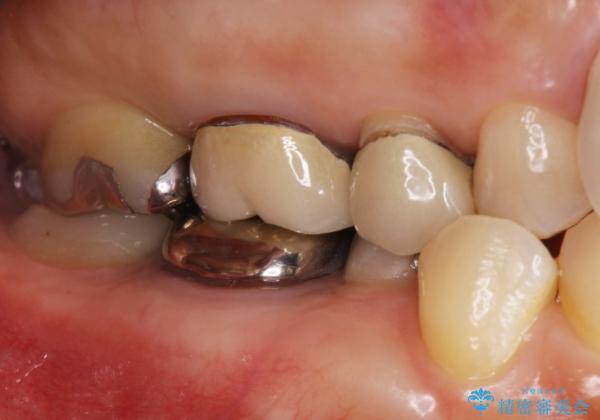

- 右上の奥歯がしみるとのことで確認すると、右上の一番奥の歯の銀歯の下が虫歯になっていました。

かなり大きな銀歯が装着されていたので、かぶせ物にて治療を行うこととなりました。

同時に右上の後ろから3番目の歯のかぶせ物も適合が悪かったので同時に治療することとなりました。

虫歯もしっかり除去して、適合の良い補綴物を装着しました。